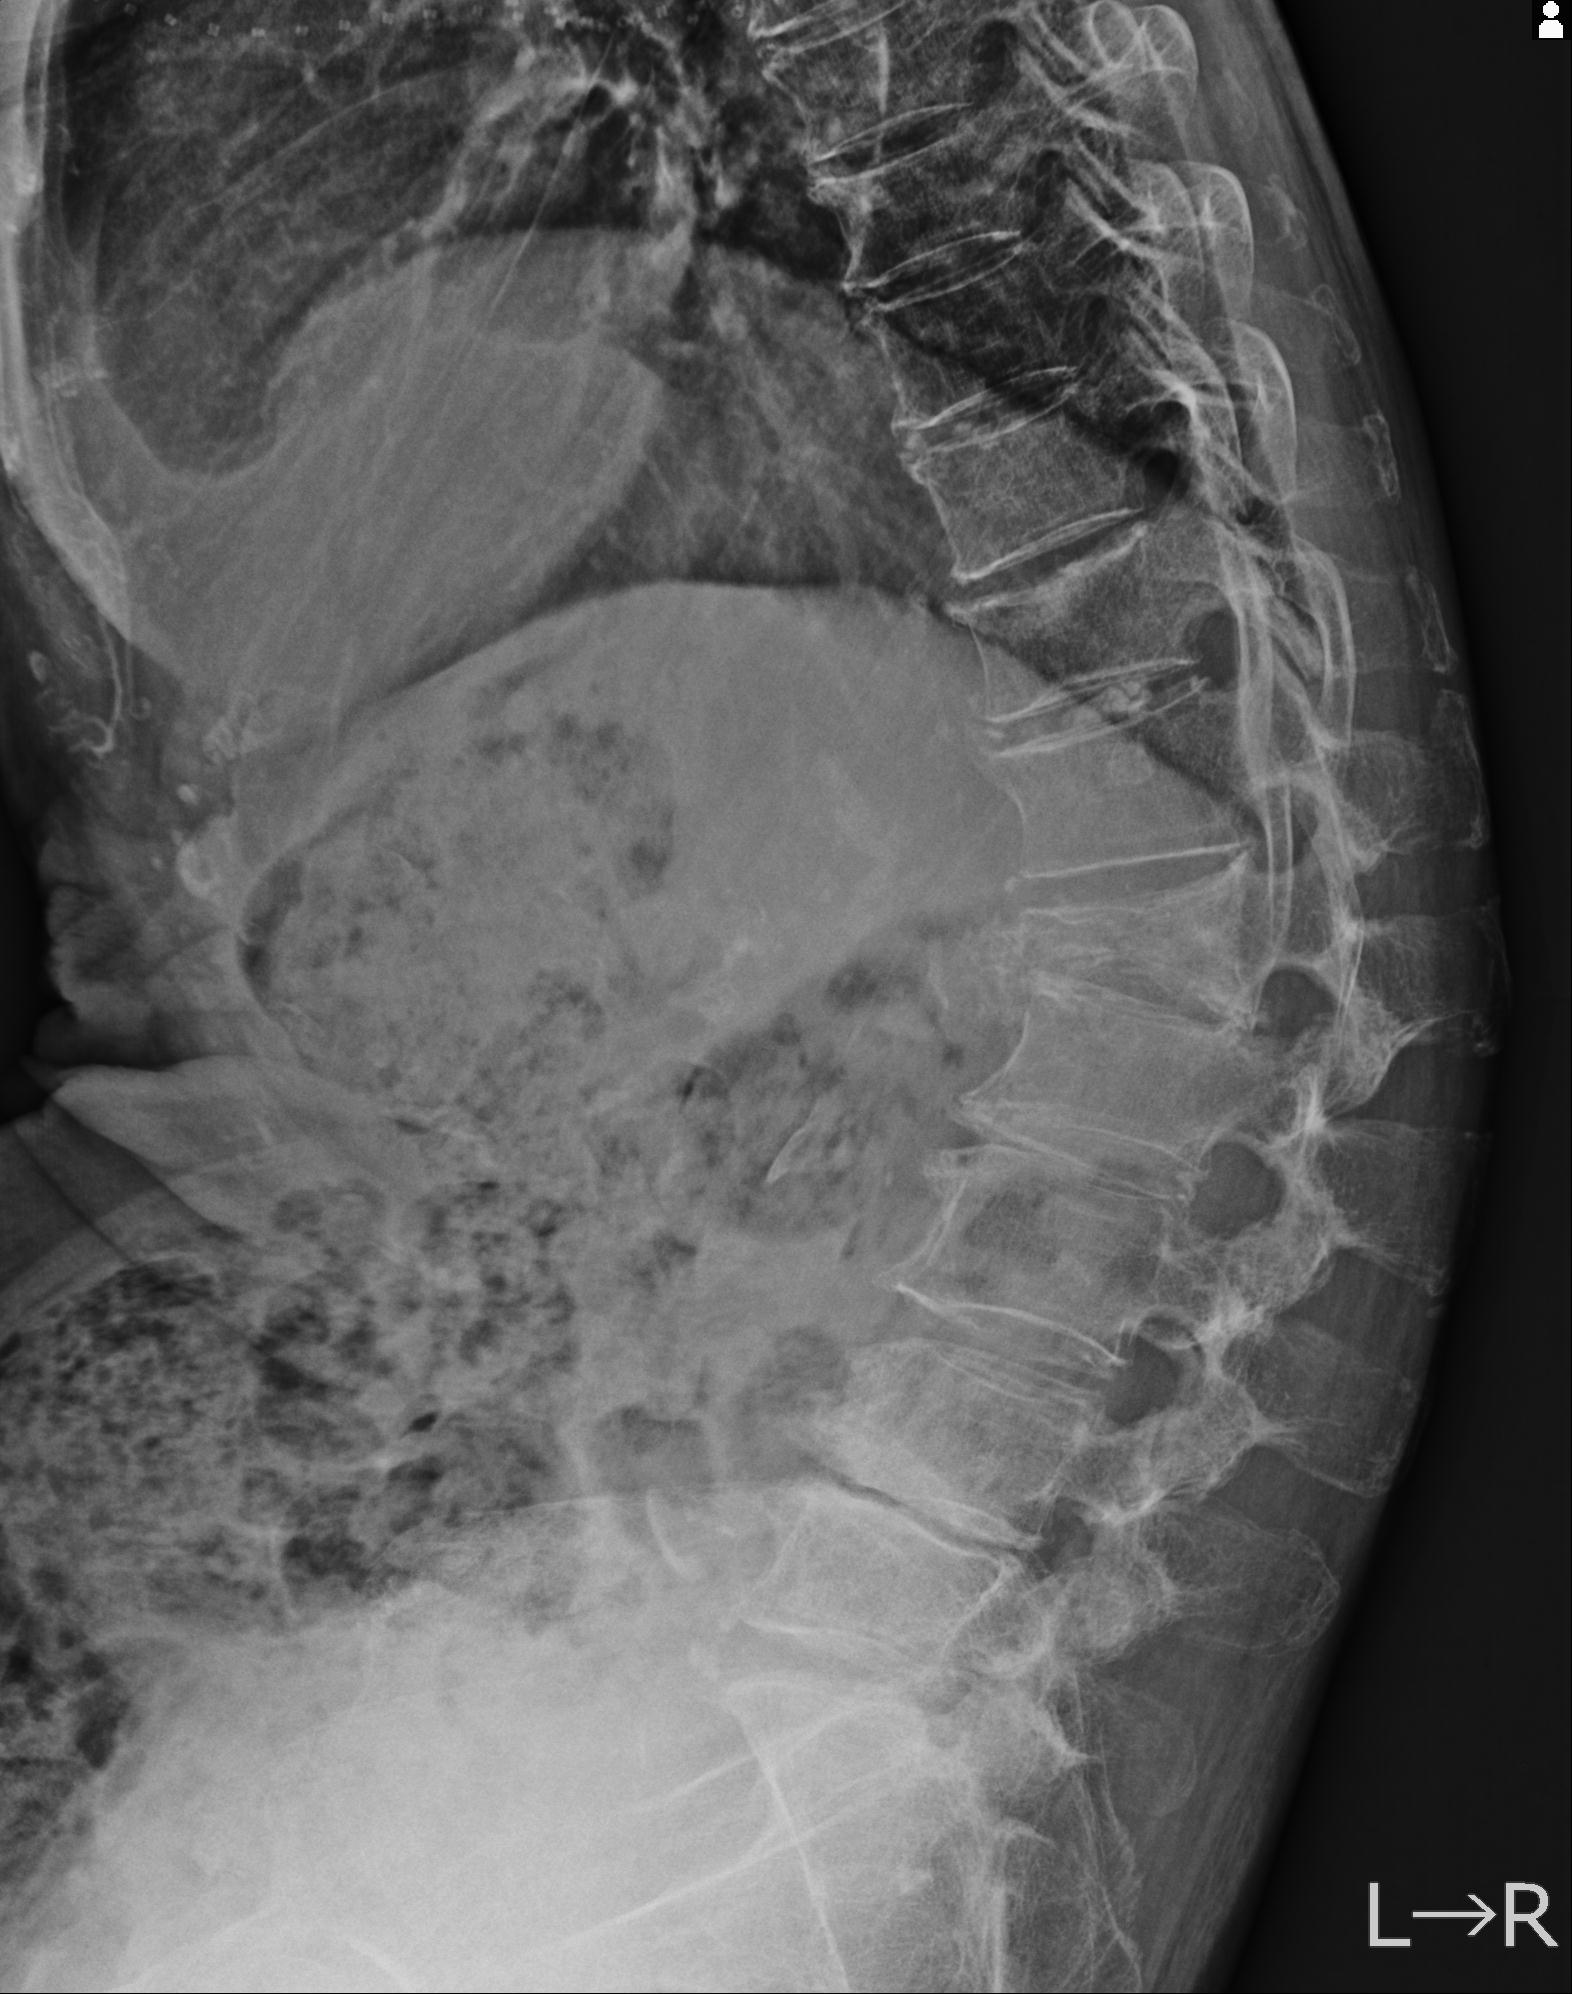

102916 2/1 と 3/22 腰椎 2R 74歳女性 LIFX